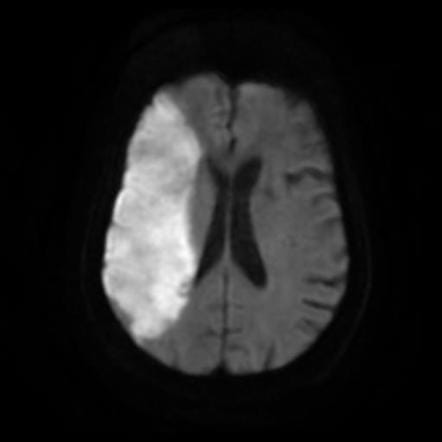

Diffusion-Weighted Imaging (DWI)

When a stroke occurs, brain cells are deprived of oxygen and start to die. DWI can contribute valuable information by detecting these changes very early on by measuring the movement of water molecules in the brain. In a healthy brain, water molecules move around freely. However, during a stroke, this movement is restricted due to cell damage. DWI picks up on these restricted movements, allowing the radiologist to pinpoint the affected areas quickly. This early detection is vital because it helps stroke clinicians make decisions about treatment options, potentially minimising the risk of long-term damage from the stroke.